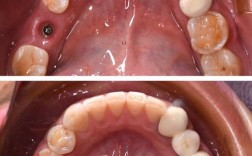

传统种植牙需切开牙龈、翻瓣暴露骨面,手术创伤较大,术后肿胀疼痛明显,恢复期常需1-2周,而微创种牙依托数字化技术与精密设备,实现了“不翻瓣”或“小切口”种植,核心优势在于精准、微创、高效,具体而言,术前通过CBCT、口扫仪获取口腔三维数据,结合计算机辅助设计(CAD)与3D打印技术,制作个性化种植导板,术中导板能精准定位种植体的位置、角度和深度,避免损伤神经、血管等重要组织,手术过程仅需局部麻醉,切口通常小于4mm,无需缝合或仅需1-2针,术后肿胀轻微,多数患者当天即可进食软食,3-5天恢复正常生活。

值得注意的是,南京微创种牙已实现“全流程数字化”:从术前的口腔数据采集、方案设计,到术中的导板导航、种植体植入,再到术后的牙冠设计与佩戴,每个环节均依托精准数据,将误差控制在0.1mm以内,对于半口缺牙患者,All-on-4微创种植技术仅需植入4颗种植体即可支撑半口牙桥,避免全口植骨,手术时间缩短至1-2小时,当天戴牙恢复咀嚼功能,大幅提升患者生活质量。